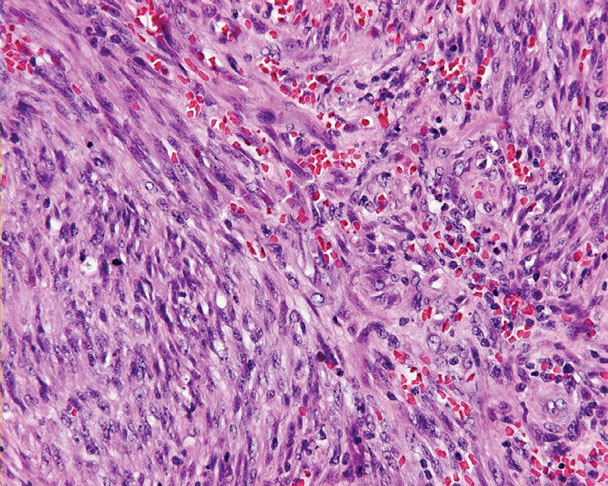

The pathology of KS plaques is more characteristic and reveals extensive vascular proliferation at all levels of the dermis with multiple dilated and angulated vascular spaces dissecting the collagen leaving a spongy network of collagen tissue. A characteristic sign of KS papules is the presence of solid cords and fascicles of spindle cells arranged between the jagged vascular channels. This biphasic angiomatous and solid tumor morphology changes to a clear-cut sarcomatous morphology with progression of the disease.

Nodular lesions consist predominantly of spindle cells arranged in bundles and interlacing fascicles and interspersed, irregular, slit-like vascular spaces without endothelial linings. Advanced lesions may display pronounced pleomorphism, nuclear atypia, and mitotic figures. At the periphery of solid tumors, (lymph) angiomatous-like portions of KS with bizarre vascular lumina and intravascular and extravasated erythrocytes, as well as siderophages, may be preserved. Erythrocytes, which appear as eosinophilic globules, are trapped within the slits and clefts formed by the spindle cells and erythrophagocytosis are occasionally observed. As in all other stages of KS, a moderate inflammatory infiltrate consisting of lymphocytes, histiocytes, plasma cells, and, sporadically, neutrophils is regularly present.